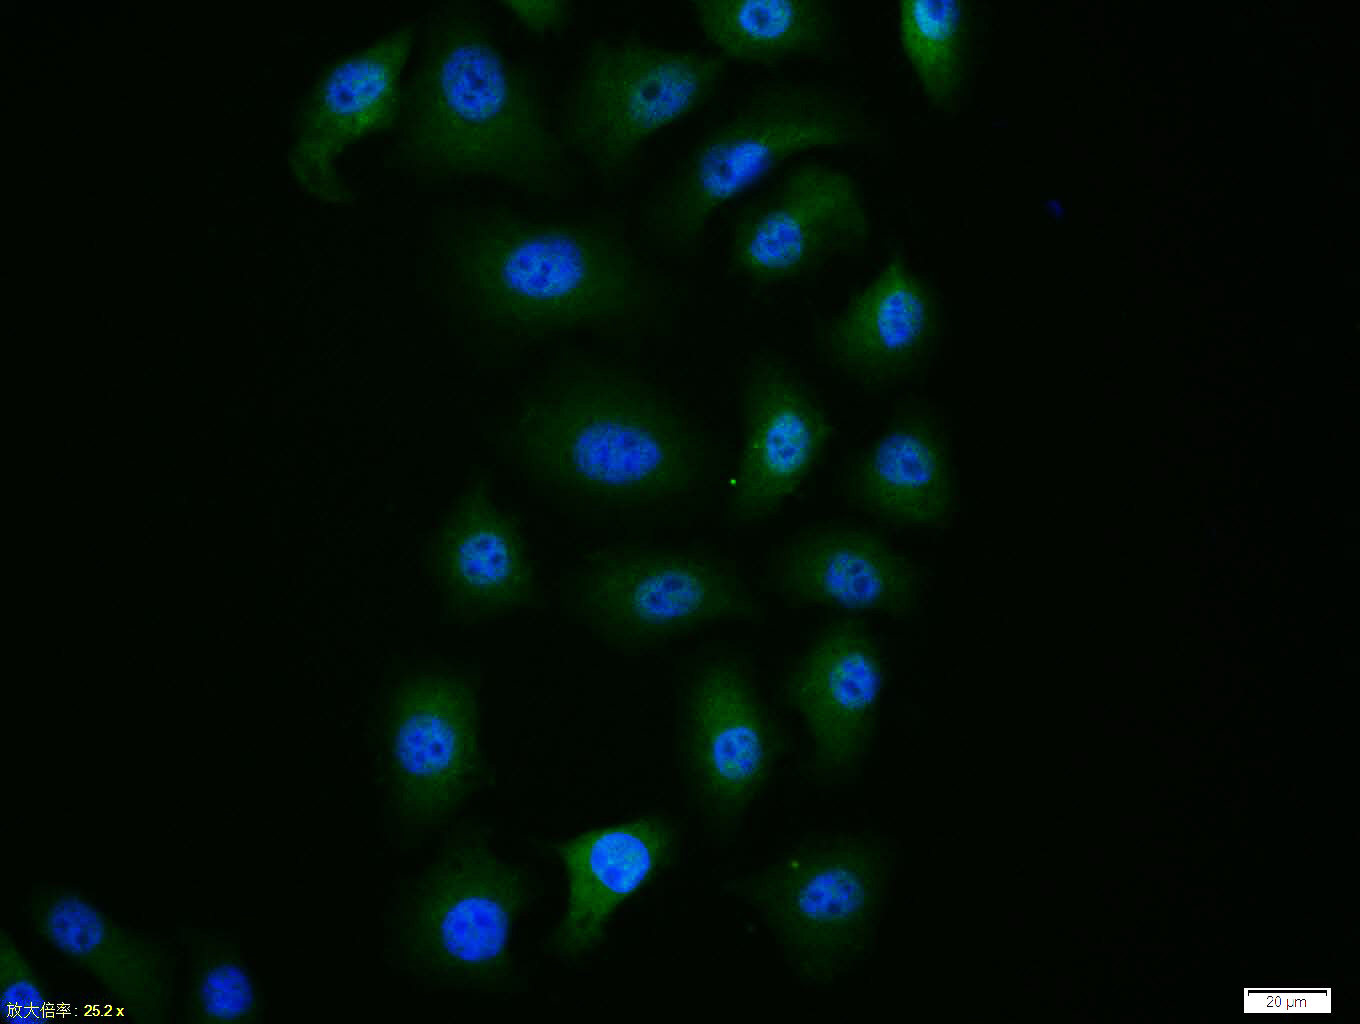

| 产品应用 | WB=1:500-2000, IHC-P=1:100-500, IHC-F=1:100-500, ICC/IF=1:100-500, IF=1:100-500, Flow-Cyt=1ug/Test Not yet tested in other applications. |

| {ICC/IF} | {1:100-500} |

| {IF} | {1:100-500} |